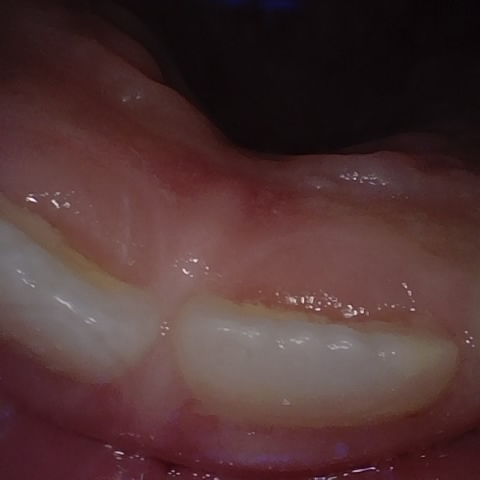

Annotated as "Bad"